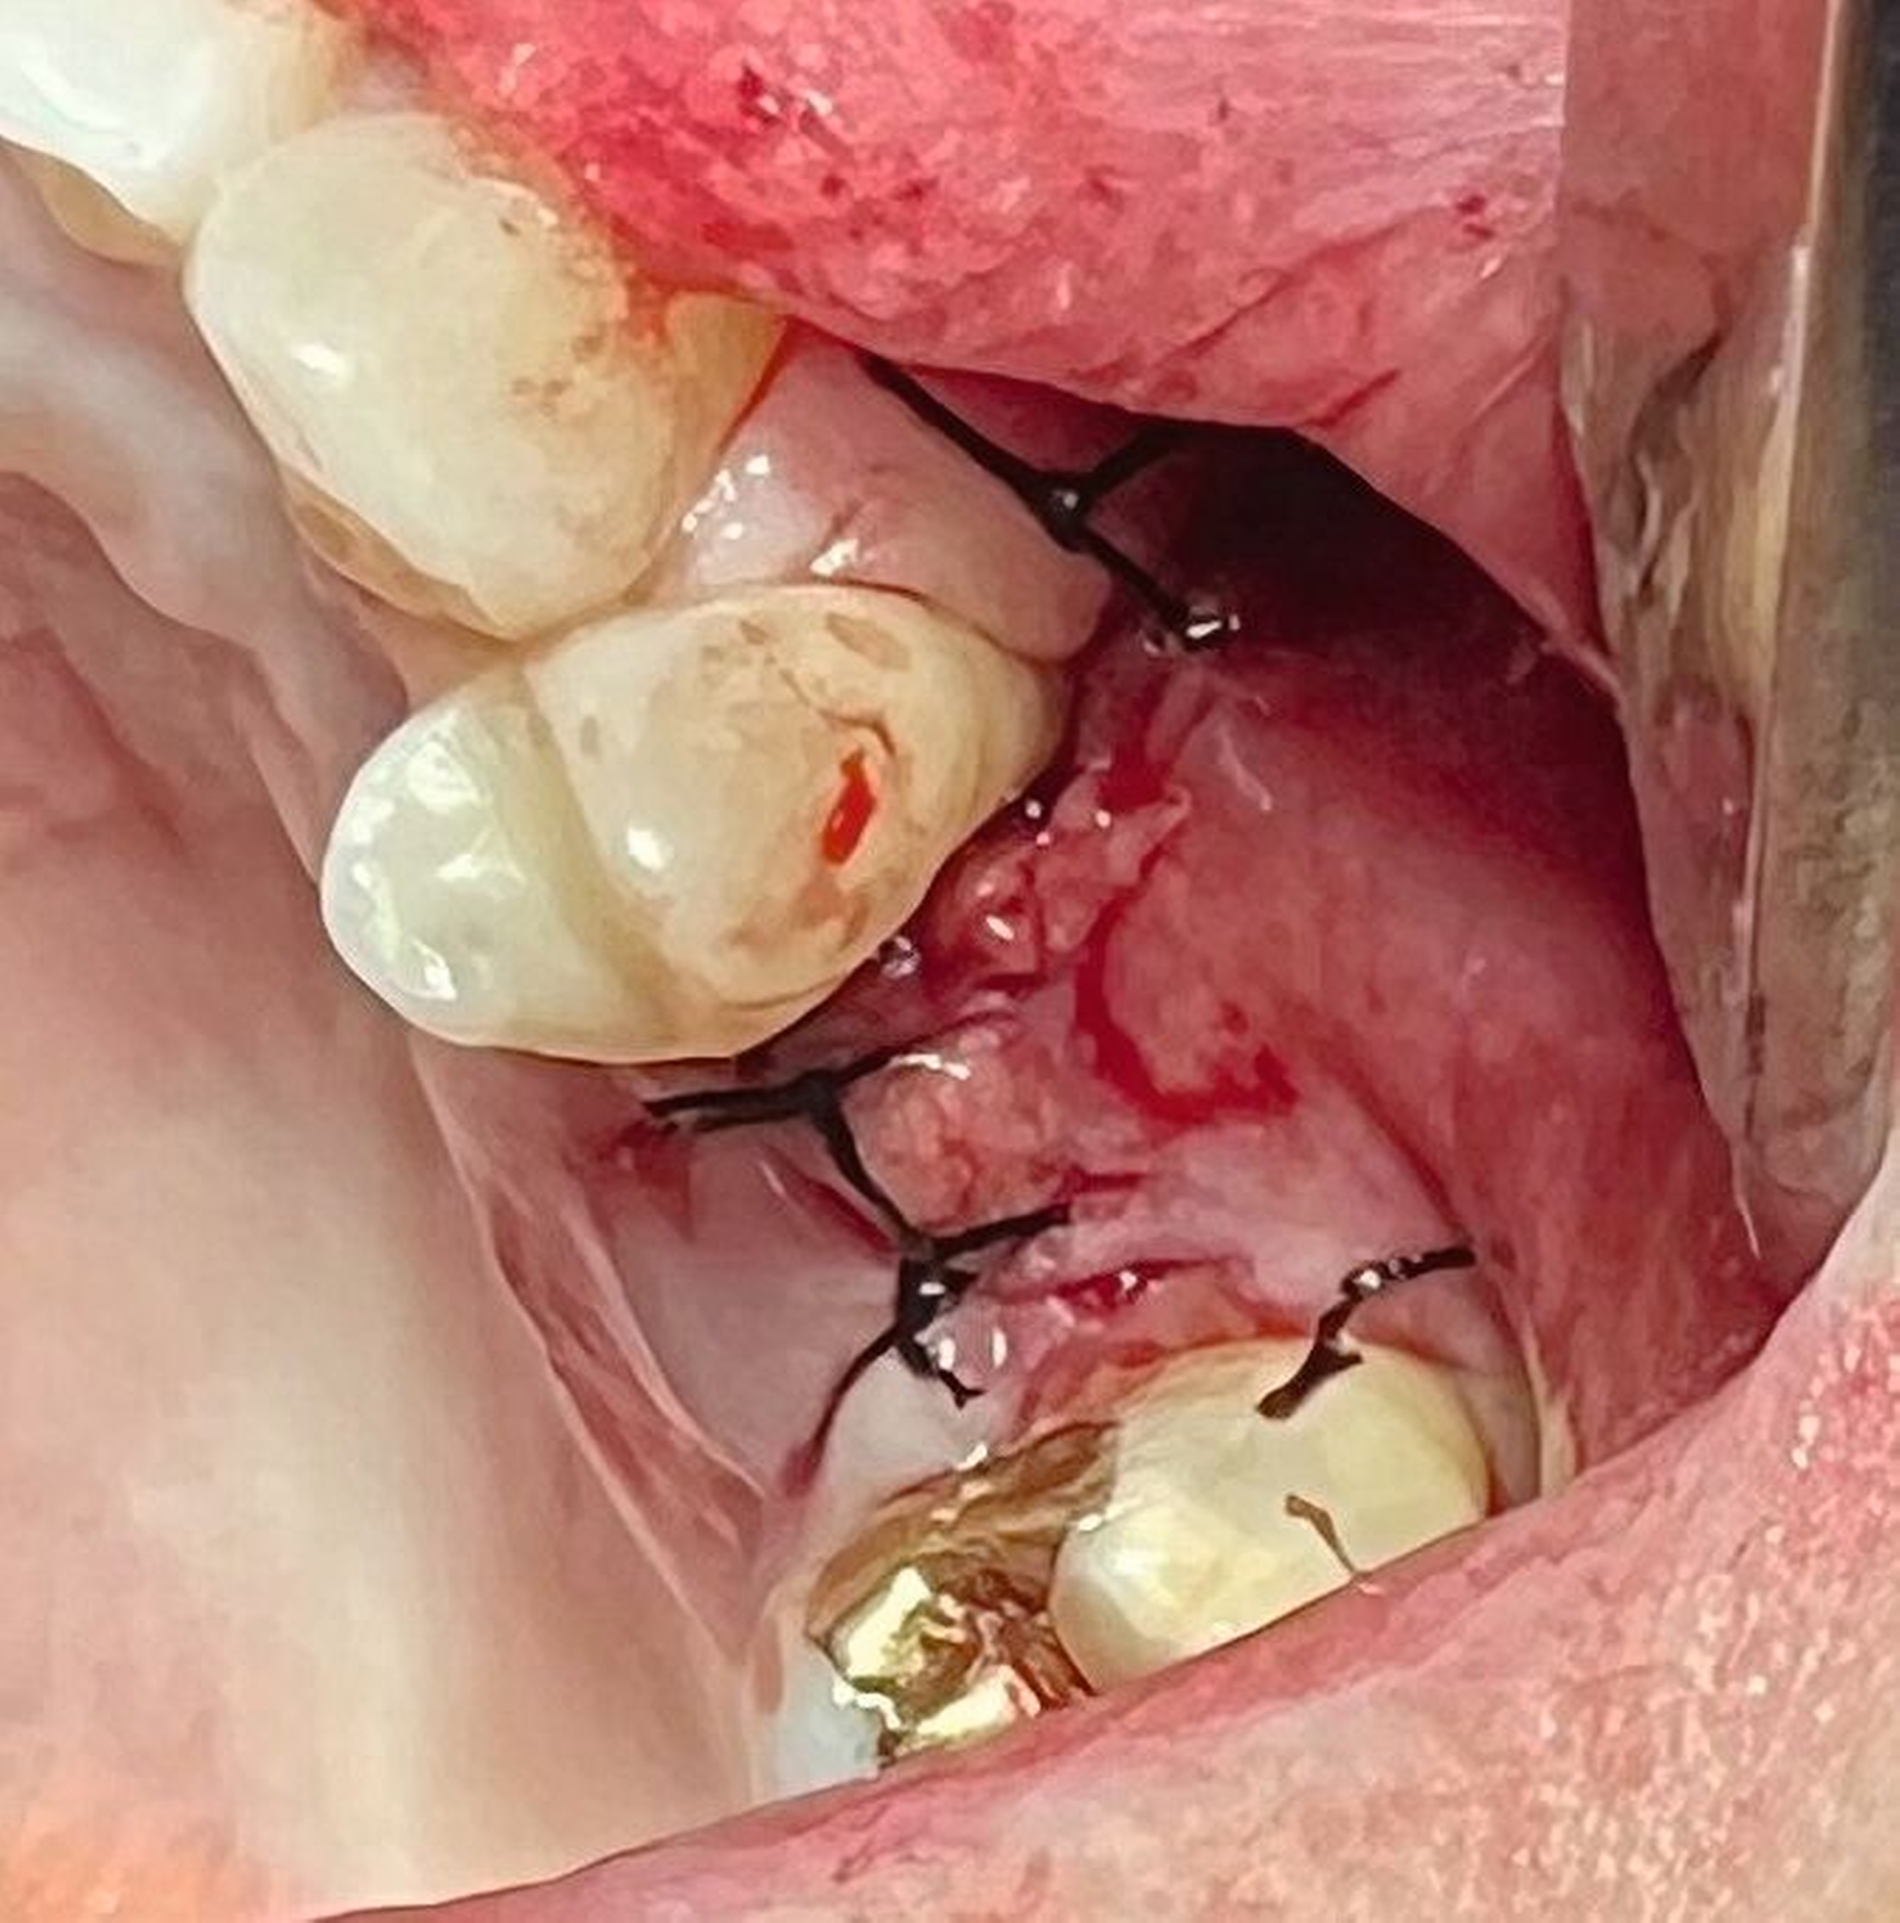

Das präoperative OPG zeigte einen generalisierten horizontalen und an den Zähnen 16 und 26 auch einen vertikalen Knochenabbau, Konkremente insbesondere im zweiten und im dritten Quadranten und in der Unterkieferfront, einen Füllungsverlust an 22, eine regelrechte Wurzelkanalbehandlung an Zahn 25, aber keine weiteren Auffälligkeiten in den umgebenden radiologischen Strukturen (Abbildung 2). Unter antibiotischer Abschirmung wurde der nekrotische Knochen einschließlich des Zahnes 25 bis zum vitalen, durchbluteten Gewebe in Lokalanästhesie abgetragen (Abbildung 3). Der Wundverschluss erfolgte mittels eines Dehnungslappens durch Periostschlitzung (Abbildung 4). Es folgte eine detaillierte Instruktion zur postoperativen Wundschonung. Eine Röntgenkontrolle wurde postoperativ durchgeführt (Abbildung 5).